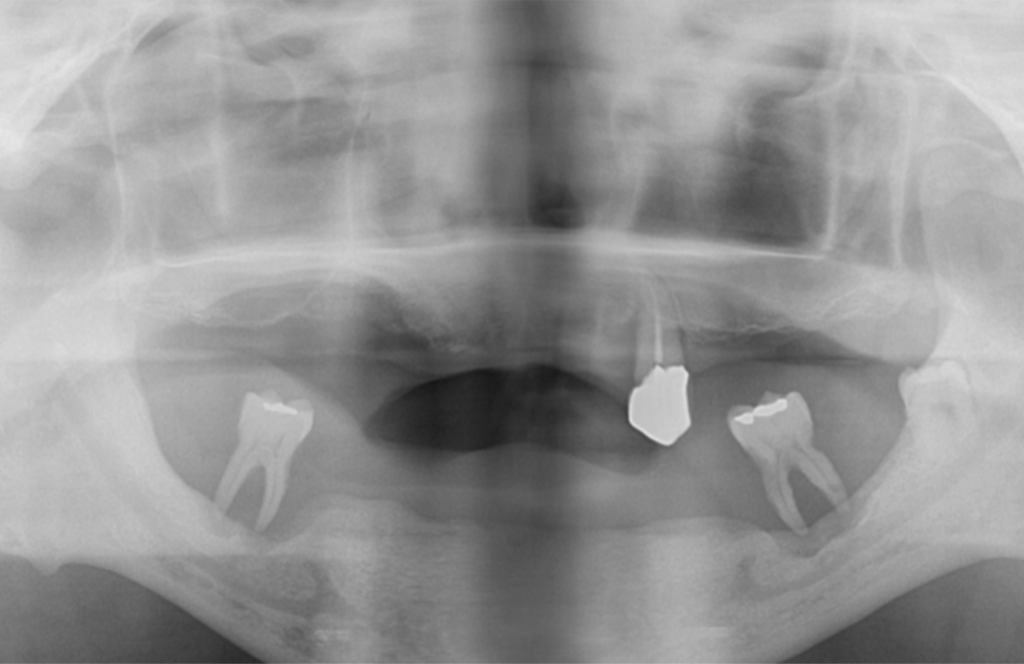

➤ 無料カウンセリング詳細精密検査・診断

歯科用CT等を用い、骨の量・質、神経や血管の位置、噛み合わせを多角的に確認。安全性を最優先した精密なシミュレーションを行います。